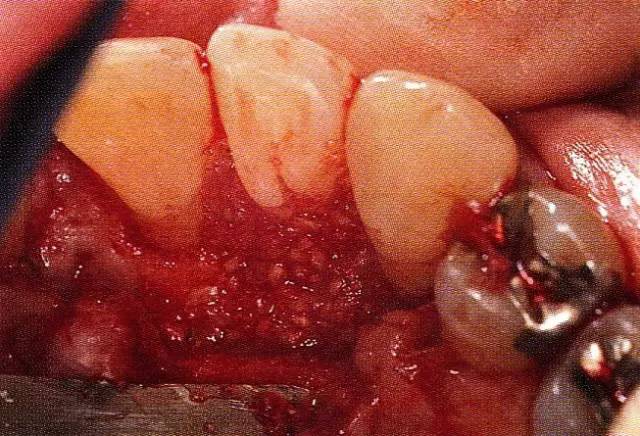

640.webp (3).jpg

▲圖7-4  術(shù)后1年2個月再翻開看的情況。與圖7-1的骨缺損狀態(tài)相比可知形成了臨床性骨再生。